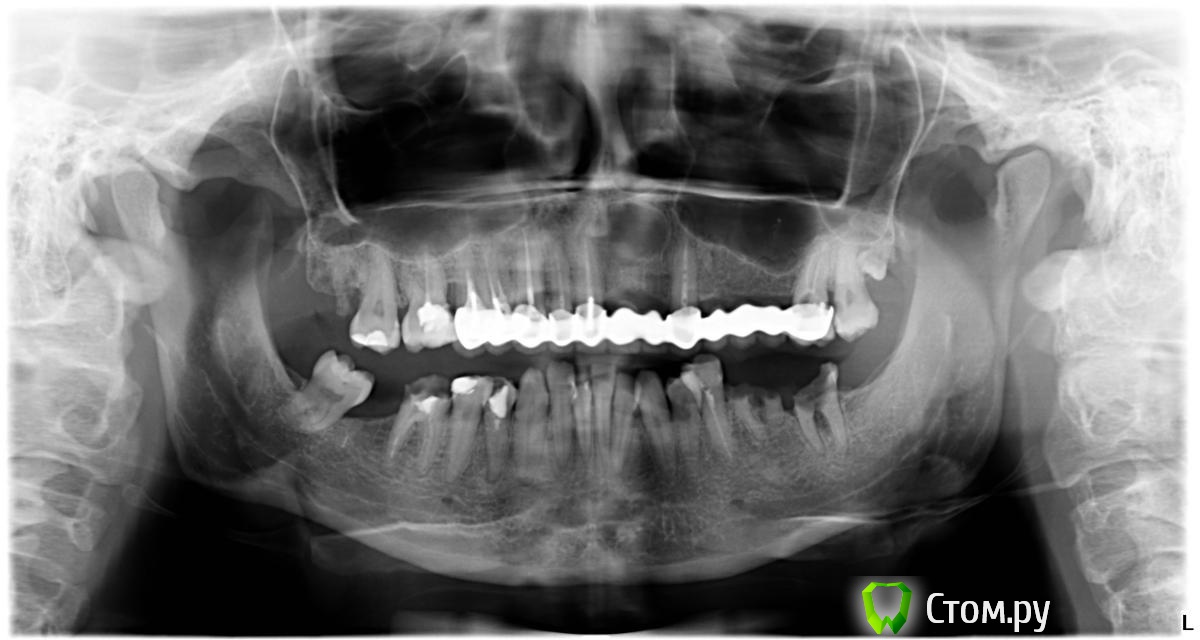

kamranchick Опубликовано 16 октября, 2014 Поделиться Опубликовано 16 октября, 2014 Доброй день уважаемые коллеги!Имеется вопрос, в начале следующей недели планируется удаление корней 3.6 и зуба 3.7С последующей имплантацицией.Так как это первая работа моя в дистальных отделах то есть вопросы.Помимо атравматичного удаления, стоит ли аугментировать лунку( в наличии есть alpha bio graft)И через сколько ориентировочно можно планировать имплантацию?Пациентка молодая, 30лет, системных заболеваний нет.Спасибо Ссылка на комментарий

kamranchick Опубликовано 16 октября, 2014 Автор Поделиться Опубликовано 16 октября, 2014 В дальнейшем планируется снятие мостовидных протезов и замена на имлпантаты Ссылка на комментарий

hemchik Опубликовано 16 октября, 2014 Поделиться Опубликовано 16 октября, 2014 на верхней челюсти киста? Ссылка на комментарий

kamranchick Опубликовано 16 октября, 2014 Автор Поделиться Опубликовано 16 октября, 2014 Пациент сегодня пришел, делали резекцию фронта, видимо без тщательной очистки, отправили на к/т, завтра посмотрим что там. А так, все снимать, лечить, и протезировать заново Ссылка на комментарий

kamranchick Опубликовано 16 октября, 2014 Автор Поделиться Опубликовано 16 октября, 2014 Со слов пациента, такое состояние полости рта, после автомобильной аварии Ссылка на комментарий

bullbull Опубликовано 16 октября, 2014 Поделиться Опубликовано 16 октября, 2014 34 и 35 восстанавливаются? Похоже там разрушение до уровня кости. Ссылка на комментарий